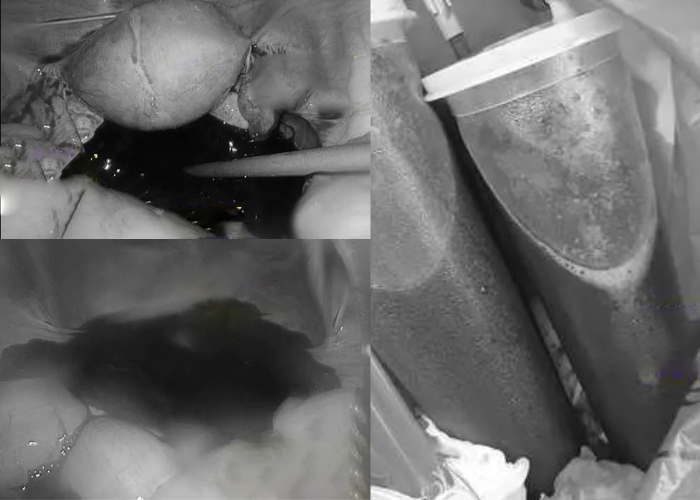

Tiến sĩ Lý Vệ Quân, bác sĩ sản phụ khoa tiếp nhận ca bệnh này cho biết: “Khi nghe mô tả triệu chứng, tôi nghi ngờ ngay khả năng vỡ hoàng thể. Kết quả kiểm tra cho thấy bệnh nhân xuất huyết ồ ạt trong ổ bụng. Lượng máu được hút ra trong ca mổ lên tới khoảng 1,5 lít. Ngoài vùng chậu, máu còn lan rộng trong khoang bụng".

Ê-kíp phải nội soi khẩn cấp, xử lý điểm rách ở buồng trứng, cắt nang hoàng thể và làm sạch ổ bụng. May mắn, buồng trứng vẫn được bảo tồn. Nhưng với tư cách vừa là bạn cấp 3 của người bạn trai, vừa là bắc sĩ điều trị thì Tiến sĩ Lý không thể không trách anh ta vài câu.

| Tổng lượng máu trong khoang bụng do vỡ hoàng thể là 1,5 lít (Ảnh BV cung cấp) |